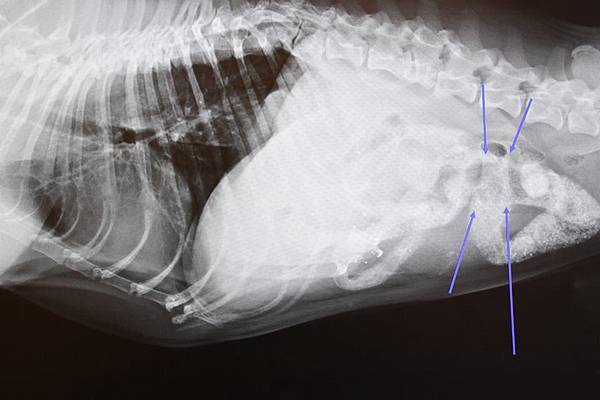

透過理學檢查及詳細的問診後高度懷疑為消化道異物阻塞

因此決定馬上安排進行消化道顯影劑連續攝影及抽血檢查

在經由影像診斷確診後和主人溝通下午立即進行腹腔手術